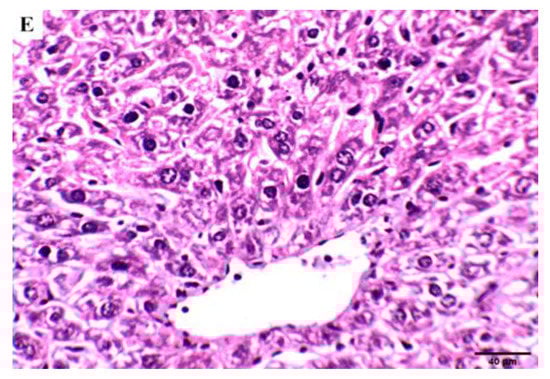

Effect of Compound 4 on the Liver Tissue of SEC-Bearing Mice

The effect of compound 4 treatment on hematological and biochemical parameters was demonstrated through liver histopathological examination (Figure 8). Liver tissue from normal control mice showed a normal anatomical structure of liver lobes and polyhedral hepatocytes with a nucleus and granular cytoplasm. Hepatocytes arranged in alternating strands with blood sinusoid forming a network around the central vein, and liver sections of normal control mice treated with compound 4 showed normal-looking liver lobules; some hepatocytes showed a hydropic degeneration and a balloon degeneration. On the other hand, degenerated balloons were visible in the SEC control group with cytoplasmic vacuolation, intranuclear cytoplasmic inclusions, and absence of cell boundaries, and liver tissue loss of membrane integrity leads to cell fusion. Hydropic degeneration of the hepatocytes and other hepatic cells had nuclear pyknosis (arrowheads) and karyolysis. Hydropic degeneration of hepatocytes, nuclear pyknosis, and karyolysis still occurred in the 5-FU group in the SEC group. On the contrary, the SEC group + compound 4 group showed liver lobules looking normal. In addition, few hepatocytes showed hydropic degeneration and activated Kupffer cells. These findings support the results previously seen after tumor volume measurement, which indicates that mice treated with compound 4 were more efficient at inhibiting tumor growth.

Figure 8.

Effect of compound 4 on the liver tissue of SEC-bearing mice: (A) normal control, (B) normal group treated with compound 4. (C) SEC control group, shows nuclear pyknosis (arrowheads) and karyolysis (arrows). (D) SEC mice treated with 5-FU still exhibit hydropic degeneration of hepatocytes, nuclear pyknosis (arrowheads), and karyolysis (arrows). (E) SEC mice treated with compound 4 (H&E stains, magnification ×200). Quantification data of the H&E analysis of liver are supported in Supplementary Table S2.